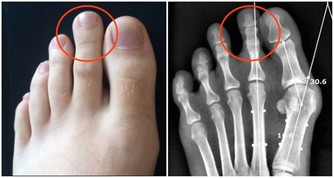

◆10腎在體合於骨,主骨生髓《素問·陰陽應像大論》說:“腎生骨髓”。腎精充盈,才能生成骨髓,而骨頭的生長發育必須要靠骨髓來營養。如果腎精不足,骨髓空虛會導致:小兒囟門遲閉、骨軟無力(先天軟骨病也是腎精不足的表現),以及中老年人骨質脆弱、容易骨折、青壯年人容易發生脊柱病變(如:脊柱變形、頸椎病、腰椎間盤突出、膨出等)。另外,牙齒也是骨頭的一部分,齒為骨之餘,《雜病源流犀燭·口齒舌病源流》說:“齒者,腎之標,骨之本也”。若腎精不足,牙齒就會鬆動,發生病變,甚至脫落。